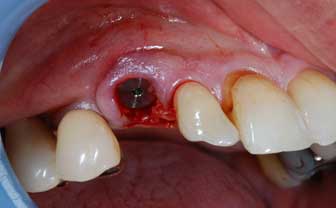

I denti irrecuperabili dell'arcata superiore ed inferiore del paziente di anni 65

sono stati sostituiti da 10 impianti, cioè protesi radicolari endo-ossee che sostengono le protesi fisse superiore ed inferiore.